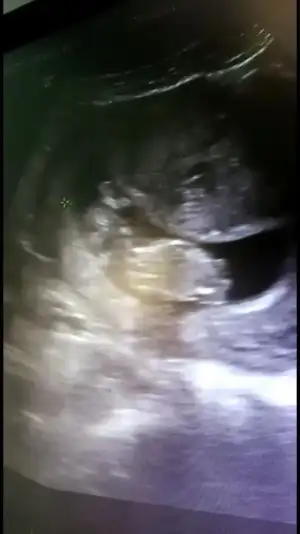

Bakarmısınız doktor erkek dedi

Merhaba, bizim icin de bir tahmininiz olur mu acaba? Normalde 12+4 ama ultrasonda 13+3 cikiyor. Allah nasip ederse gelecek ayin 20sinde kesin ogrenecegiz cinsiyeti. Yarin Nifty testi icin kan verecegim 😁

20210429_124951.jpg

20210429_124925.jpg